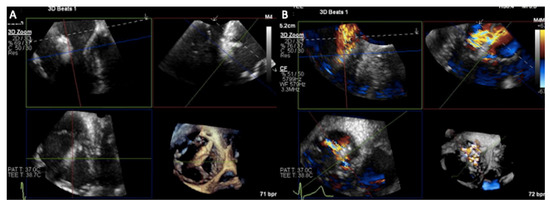

3.1. Two-Dimensional and Three-Dimensional Transesophageal Echocardiography

- Hahn, R.T.; Kodali, S.K. State-of-the-art intra-procedural imaging for the mitral and tricuspid PASCAL Repair System. Eur. Heart J. Cardiovasc. Imaging 2022, 23, e94–e110. [Google Scholar] [CrossRef]

- Hahn, R.T.; Nabauer, M.; Zuber, M.; Nazif, T.M.; Hausleiter, J.; Taramasso, M.; Pozzoli, A.; George, I.; Kodali, S.; Bapat, V.; et al. Intraprocedural Imaging of Transcatheter Tricuspid Valve Interventions. JACC Cardiovasc. Imaging 2019, 12, 532–553. [Google Scholar] [CrossRef]

- Ro, R.; Tang, G.H.L.; Seetharam, K.; Khera, S.; Sharma, S.K.; Kini, A.S.; Lerakis, S. Echocardiographic Imaging for Transcatheter Tricuspid Edge-to-Edge Repair. J. Am. Heart Assoc. 2020, 9, e015682. [Google Scholar] [CrossRef] [PubMed]